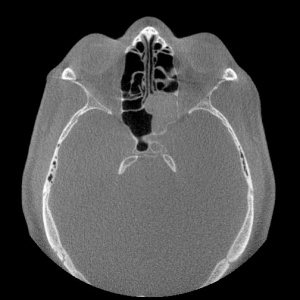

Computed tomography (CT) of the orbit is the initial imaging modality of choice for diagnosing and characterizing the extent of orbital aspergillosis, as it is quick and effective. Aspergillus appears as isodense, heterogenous lesions affecting the paranasal sinuses with calcification and bony erosion. The sphenoid sinus is the most commonly affected paranasal sinus, which is postulated to be related to its low oxygen content and acidic environment (Figures 1 and 2). The presence of patchy hyperattenuation is also considered an indirect indicator of fungal disease.[16] MRI reveals hypointense lesions on T1 and T2-weight images in contrast to neoplastic and bacterial lesions which are hypertense on T-2 weighted images.[8] MRI is generally preferred to CT in evaluating the orbital apex, cavernous sinus, and optic nerve changes.